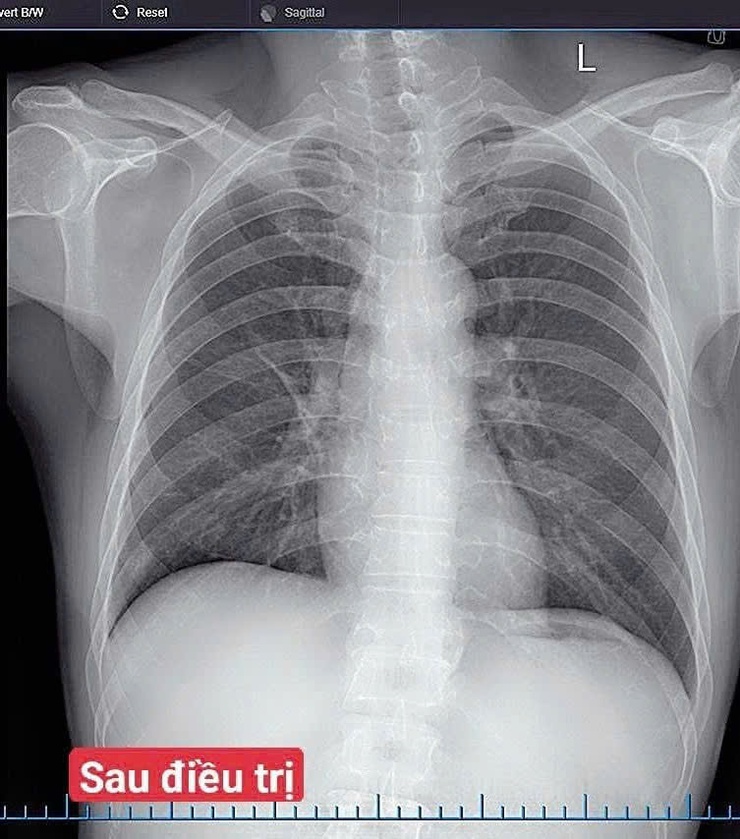

Điều trị thành công ca viêm phổi cộng đồng trên bệnh nhân xơ gan, viêm gan B tại Bệnh viện Đa khoa Vân Đình- Ảnh 2.

Hình ảnh trước và sau điều trị của người bệnh

Sau 7 ngày điều trị, tình trạng bệnh nhân cải thiện rõ rệt: hết sốt, giảm ho, giảm đau ngực, ăn ngủ tốt, chỉ số sinh tồn ổn định.